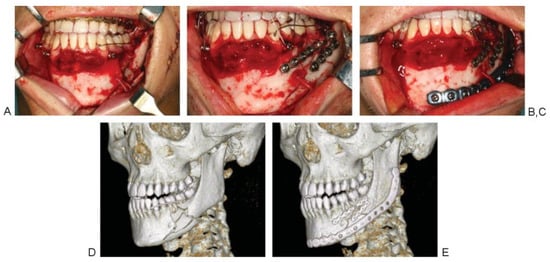

The posterior plate end is commonly fixed to the angle/ ramus. Depending on the dimension of the defect/fracture zone, the anterior plate end may be fixed to the symphyseal region, working around the mental nerve unilaterally (unilateral crossway situation; Figure 1A). Alternatively, bilateral handling of the mental nerves will be required if the anterior plate end crosses the symphysis into the contralateral parasymphyseal and body region past the contralateral mental foramen (bilateral crossway situation), for example, in ante- rolateral involvement of the mandible (Figure 1B).

Figure 1. (A) Hemimandibular MMPRP [Synthes Maxillofacial, Paoli, PA] placement for bridging the ramus and body region. The MMPRP underpasses the mental nerve unilaterally (unilateral crossway situa- tion). Screw fixation of the reconstruction plate at the ipsilateral ramus and parasymphysis/symphysis. (B) MMPRP placement for extended bridging of the ramus, the body, and the symphyseal region. The MMPRP underpasses both mental nerves (bilateral crossway situation). Screw fixation of the reconstruction plate at the ipsilateral ramus and contralateral body, past the mental foramen. Abbreviation: MMPRP, MatrixMANDIBLE Preformed Reconstruction Plate.

Especially in cases of comminuted fractures, single frag- ments can be fixed after reduction by miniplates to simplify the fracture (Figure 2). Subsequent to the anatomical reduc- tion of fragments (comminuted fractures, nonunions), bone curettage, or partial resection (benign tumors, osteonecrosis), the best fitting MMPRP is selected. There are rigid metal sizers coming in three variants (small, medium, large) that serve as replicas to gauge the nonbendable centerpiece of the MMPRPs either for the left or right hemimandible. The most suitable sizer is introduced through the space below one of the two nerve loops posteriorly and aligned from the angle and ramus continuing over the body and the para- symphysis region to the mandibular midline to check for precise adaptation. It is removed afterward.

Figure 2. Patient with a comminuted fracture of the left mandibular body, representing a unilateral crossway situation. (A) Operative findings. (B) MMF screws and wires provide for mandibulomaxillary fixation and the single fragments are fixed after reduction by using miniplates. (C) MMPRP [Synthes Maxillofacial, Paoli, PA] is finally applied after it is threaded underneath the mental nerve loop overhead the lateroinferior border of the mandible. (D) Preoperative CT imaging. (E) Postoperative CT imaging showing good adaption and fit of the plate. Abbreviations: CT, computed tomography; MMF, maxillomandibular fixation; MMPRP, MatrixMANDIBLE Preformed Reconstruction Plate.